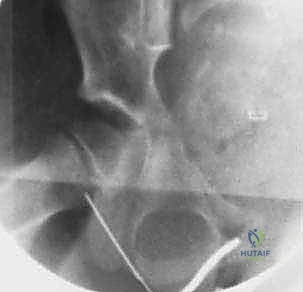

- الموجات فوق الصوتية (Ultrasound): هي الأداة الذهبية والأسرع لتأكيد وجود ارتشاح أو تجمع سوائل (Effusion) داخل كبسولة مفصل الفخذ. يمكن إجراؤها في العيادة أو الطوارئ فوراً.

- الأشعة السينية (X-rays): تُجرى لاستبعاد وجود كسور أو أورام. في الأيام الأولى للالتهاب القيحي، قد تظهر الأشعة طبيعية، أو قد تظهر اتساعاً في المسافة المفصلية بسبب تجمع الصديد، أو خلعاً جزئياً لرأس الفخذ. التغيرات العظمية المدمرة لا تظهر إلا في مراحل متأخرة (وهو ما نسعى لتجنبه).

4. بزل المفصل (Arthrocentesis) - المعيار الذهبي

إذا أكدت الموجات فوق الصوتية وجود سائل، وكانت الأعراض السريرية والمخبرية تشير إلى التهاب قيحي، فإن الخطوة الحاسمة هي سحب عينة من هذا السائل (تحت توجيه السونار وبمخدر موضعي أو عام).

* إذا كان السائل المسحوب صديدياً (قيحياً)، يتم تأكيد التشخيص بنسبة 100%.

* يتم إرسال العينة فوراً للمختبر لإجراء صبغة جرام (Gram Stain) لمعرفة نوع البكتيريا مبدئياً، وعمل مزرعة بكتيرية (Culture and Sensitivity) لتحديد المضاد الحيوي الأنسب بدقة متناهية.